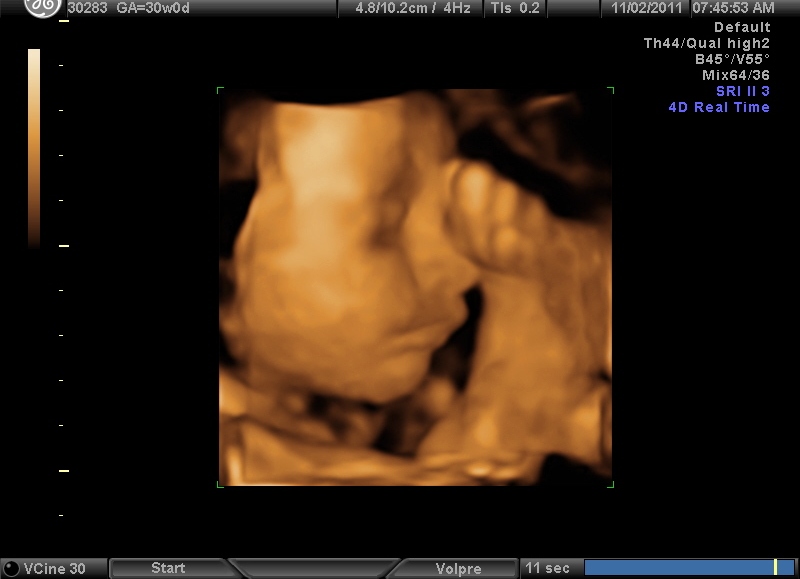

And here is a photo for you: